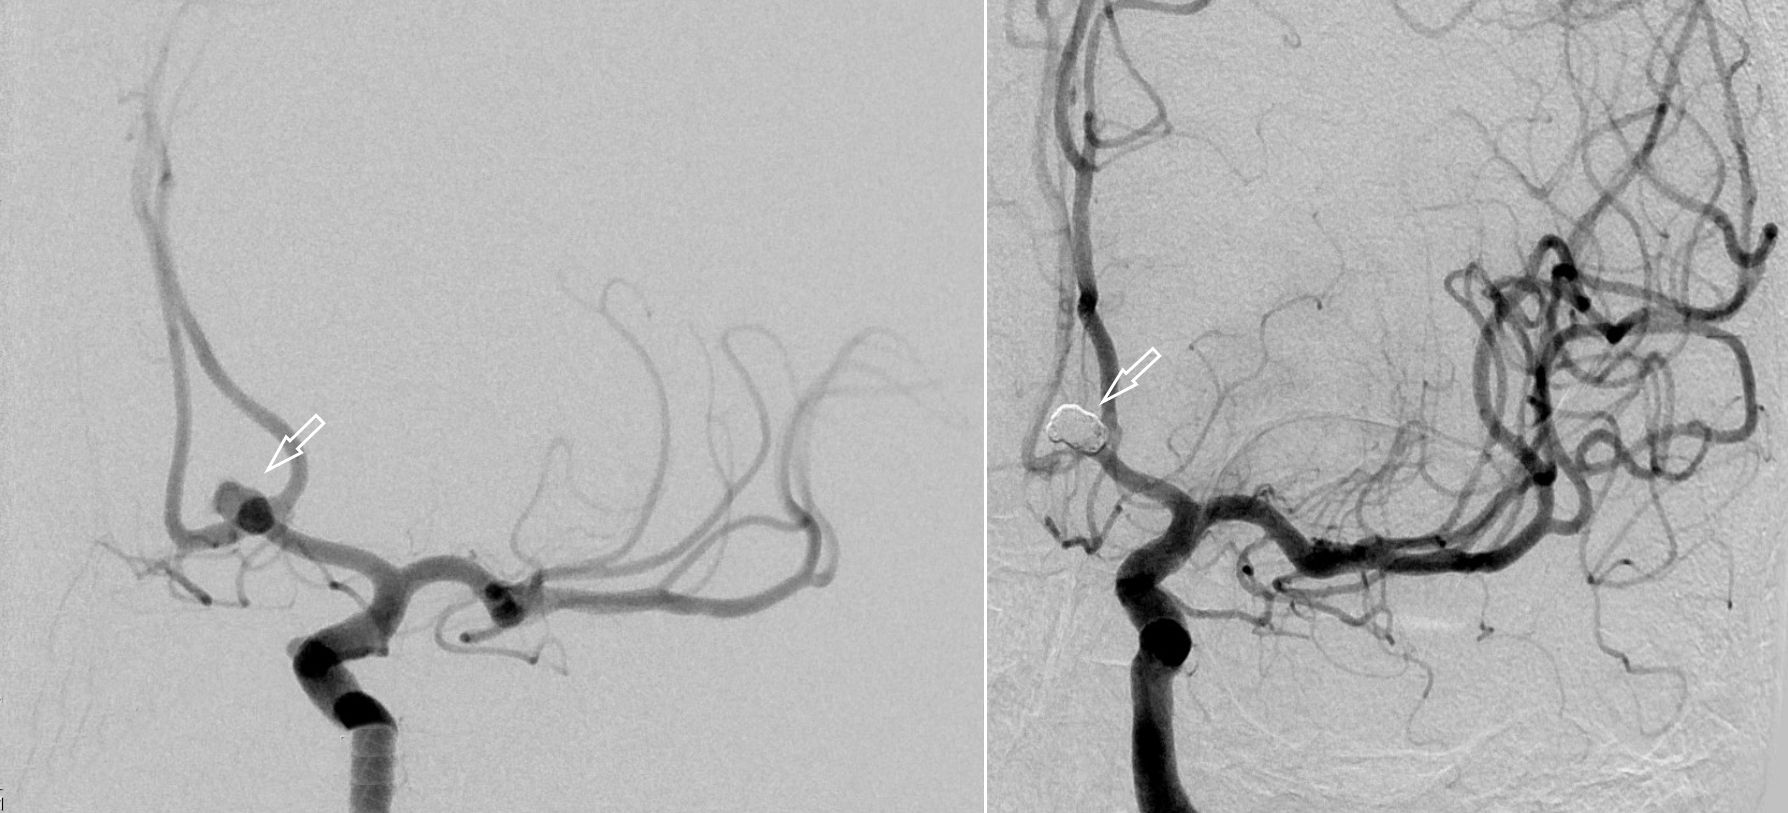

Angiographiesche Darstellung eines Aneurysmas

Angiographiesche Darstellung eines Aneurysmas vor (links) und nach (rechts) dem Coiling